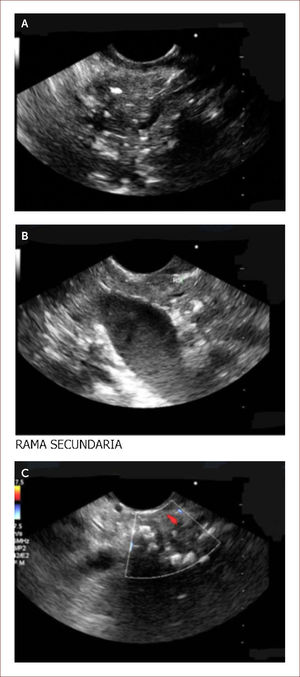

Ha sido difícil establecer por imágenes criterios claros de diagnóstico. Es en este punto donde el EUS del páncreas cobra su valor. Existen unos criterios estándar y otros llamados de Rossemont 8. Las características del parénquima pancreático en PC a evaluar son: la presencia de focos y bandas hiper-ecoicos, presencia de lóbulos y quistes. Y las características dependientes del ducto son: dilatación del conducto principal, irregularidad, realce, ramas secundarias visibles y cálculos 8. Figura 5.

Paciente de 29 años. Debutó con diabetes y dolor de abdomen. Historia de alcoholismo y tabaquismo. Dentro de los estudios le envían para EUS y vemos lo siguiente. En la imagen A se observan calcificaciones y bandas fibrosas del parénquima del páncreas. Un páncreas que es irregular. En la B se ven las misma calcificaciones y ramas secundarias. En la C se ve un conducto de Wirsung dilatado y lleno de cálculos. Todo lo anterior lo diagnostica como una pancreatitis crónica, ya que cumple con más de 5 criterios de Rossemont. Por medio de esta imagen se decidió manejo médico con cuidado nutricional y enzimas pancreáticas a dosis adecuadas. El paciente tiene Ca 19-9 normal. Su dolor se ha controlado. En caso de reactivación de su cuadro sintomático se hará biopsia por EUS. Por la dilatación del conducto y la presencia de cálculos podría ameritar intento de manejo endoscópico o de una cirugía derivativa de su conducto principal.

Para efectos del diagnóstico, se da un punto a cada factor, con más de cinco puntos aumenta la sensibilidad de que sea una pancreatis crónica, con menos de dos es poco probable, entre dos y cuatro hay alta sospecha 8.